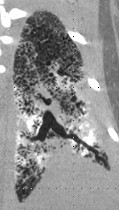

The PAM mouse model study was inspired by a patient seen by Dr. McCormack in 2011 at UC Medical Center. The woman had been diagnosed with PAM as a child in Jordan and developed exertional dyspnea at the age of 54, a typical pattern for PAM. Chest examination revealed bibasilar crackles, pulmonary function tests revealed mild restriction and reduced diffusing capacity, and a six-minute-walk test revealed normal exercise capacity with mild exertional desaturation to 88%.1 Chest X-ray showed fine hyper dense lower lung zone nodular opacities, and computed tomography of the chest showed symmetrical lower lobe predominant micronodular calcifications along bronchovascular bundles and interlobular septal thickening, findings pathognomonic for PAM.1

Chest computed tomography (CT) of patient with PAM showing symmetrical lower lobe predominant micronodular calcifications along bronchovascular bundles and interlobular septa.